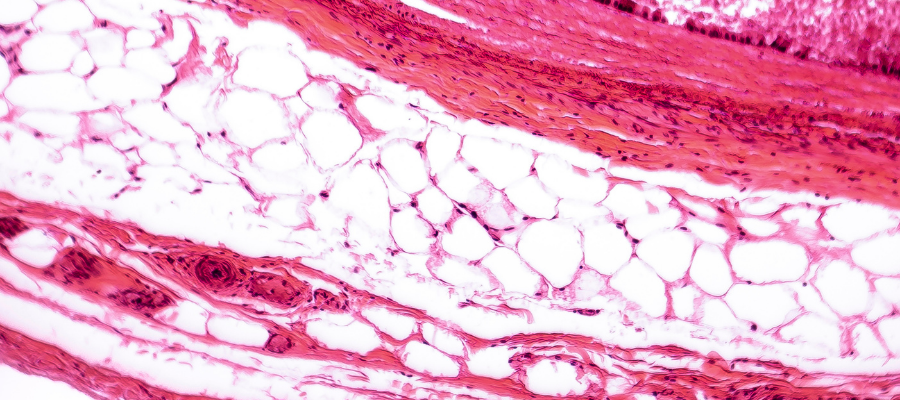

Im menschlichen Körper gibt es verschiedene Formen von Bindegewebe. Diese sind teilweise deutlich unterschiedlicher Struktur und perfekt an die jeweiligen Anforderungen angepasst. In diesem Zusammenhang wird vor allem zwischen dem lockeren und straffen Bindegewebe unterschieden.

Während das straffe Bindegewebe vielen Strukturen im Körper eine gewisse Stabilität oder mechanische Eigenschaften verleiht (Bänder, Sehnen), ist das lockere Bindegewebe vergleichbar mit einem feinen Netz, das sowohl Organe stabilisiert, sie aber auch stützend umgibt und an ihrer Position im Körper fixiert (hierbei wird auch vom sog. Interstitium gesprochen – dem Zwischengewebe). Im Falle bestimmter Organe, wie bspw. der Lunge, gewährleistet das lockere Bindegewebe darüber hinaus auch eine gewisse Beweglichkeit, die hier für die Ausdehnung während der Atmung wichtig ist.

Neben dem lockeren und straffen Bindegewebe finden sich im Organismus noch weitere Formen, wie das bekannte Stützgewebe (Knochen und Knorpel) sowie weniger stark vertretene, jedoch hoch spezialisierte Formen, wie das retikuläre Bindegewebe in Organen des Immunsystems.

Der Aufbau des Bindegewebes

Aufgebaut ist das Bindegewebe aus Strukturproteinen wie Kollagen oder Elastin. Die Kollagenstruktur variiert je nach Funktion von Gewebe zu Gewebe. Aktuell sind 28 unterschiedliche Kollagentypen bekannt. Damit ist Kollagen mit 30 % das anteilig am meisten vorkommende Protein im menschlichen Organismus1,2,3.

Die spezifischen Eigenschaften der unterschiedlichen Bindegewebsformen im Organismus hängen u.a. davon ab, welche der 28 Kollagentypen im jeweiligen Gewebe vorhanden sind. So wird das Bindegewebe z.B. fester oder lockerer, je nachdem wie dicht die Fasern eines Kollagen-Typs auftreten.